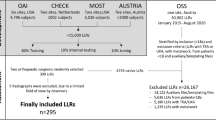

A retrospective study was conducted using previously collected WBCT scans of patients with unilateral syndesmotic instability. One-hundred and forty-four bilateral ankle WBCT scans were evaluated (48 unstable, 96 control). We developed three deep learning models for analyzing WBCT scans to recognize syndesmosis instability. These three models included two state-of-the-art models (Model 1—3D Convolutional Neural Network [CNN], and Model 2—CNN with long short-term memory [LSTM]), and a new model (Model 3—differential CNN LSTM) that we introduced in this study.